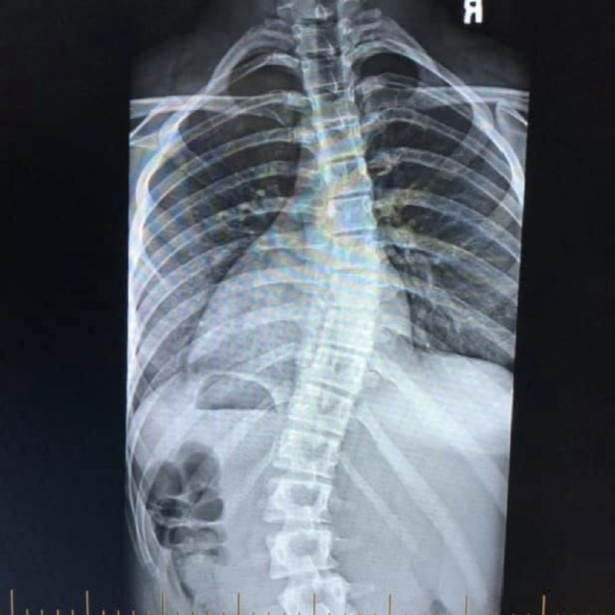

In December of 2019 I was diagnosed with scoliosis at the age of 15. I always thought the achey back pain was just from long hours in the dance studio and the insane flexibility I had. But over a few months leading up to my diagnosis I noticed the pain gradually increasing. A friend recommended a trip to the chiropractor and within minutes of being seen they told me I needed to get an x-ray. It was not long before I found out I had not just one, but two curves. I was devastated. All the negative thoughts came rushing through my head and the fear I had of doctors only worsened.